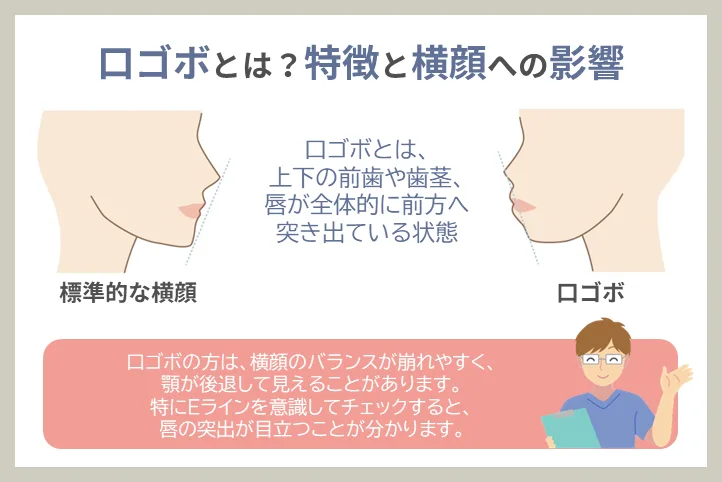

口ゴボとは?特徴と横顔への影響

口ゴボとは、上下の前歯や歯茎、唇が全体的に前方へ突き出ている状態を指します。正式には「上下顎前突(じょうげがくぜんとつ)」と呼ばれ、骨格のズレや歯並びの問題によって引き起こされます。

口ゴボの特徴

- 唇が閉じにくく、リラックスした状態でも口が少し開いてしまう

- 横顔を見たときにEライン(鼻・唇・顎を結ぶライン)よりも唇が前に出ている

- 正面から見ると口元がもっこりして見える

- 口角が下がりやすく、不機嫌な印象を与えることがある

横顔への影響

口ゴボの方は、横顔のバランスが崩れやすく、顎が後退して見えることがあります。特にEラインを意識してチェックすると、唇の突出が目立つことが分かります。